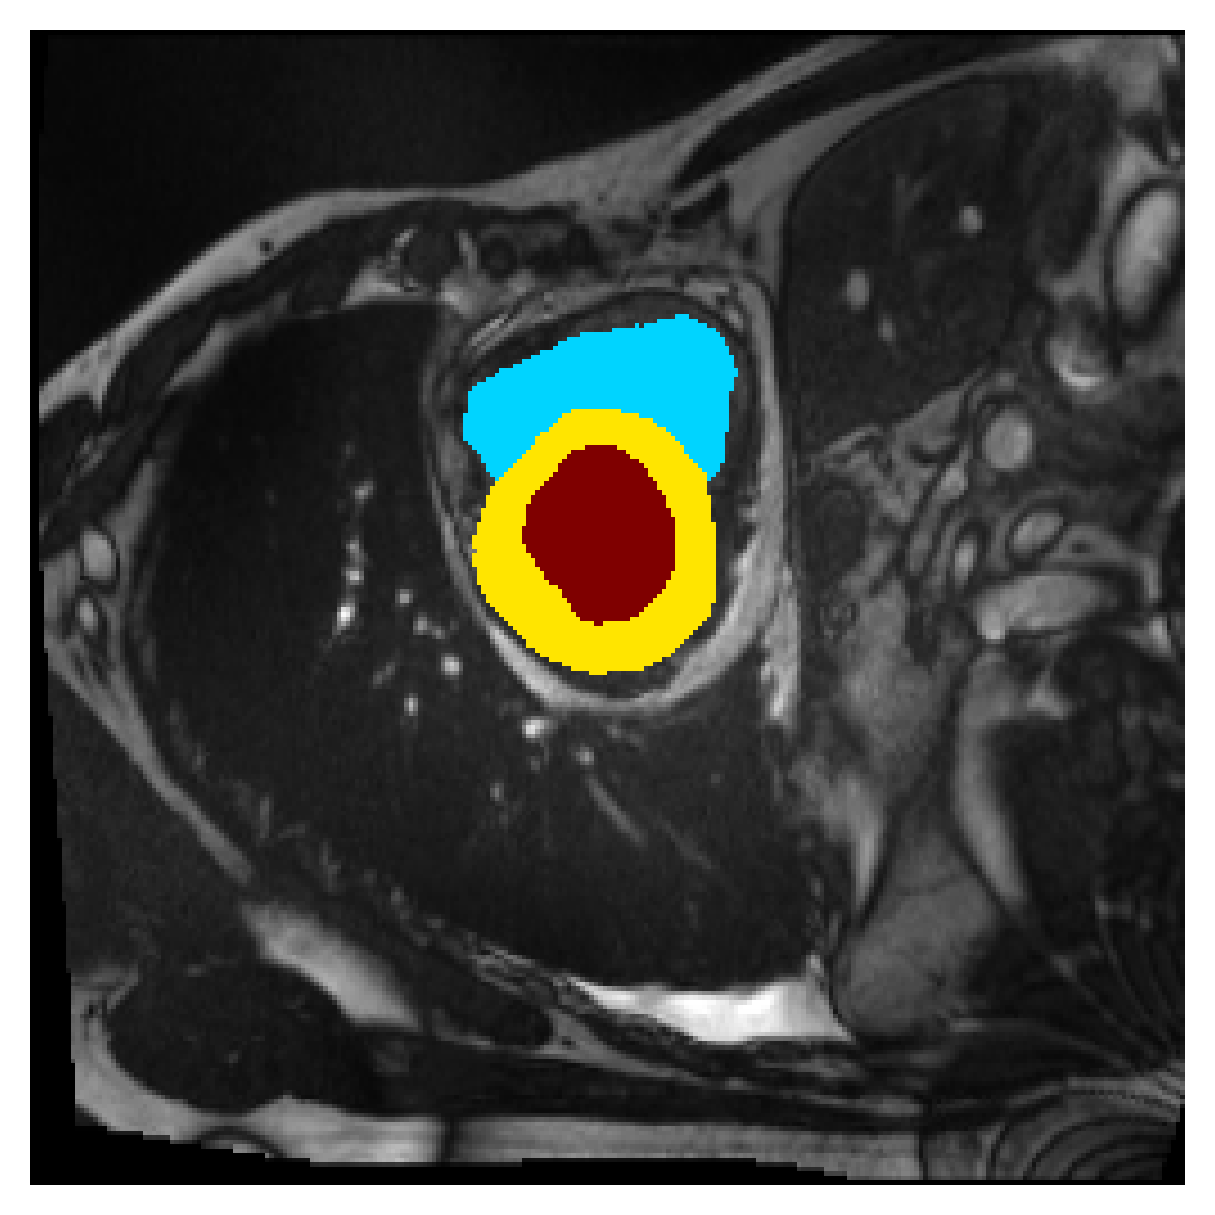

Qualitative comparison

| (a) Ground truth | (b) , full | (c) , weak | (d) |

| (full) | supervision | supervision | |

| (e) | (f) | (g) | (h) CRF-loss |

In Figure 6 we provide qualitative results on a number of randomly chosen test set slices. Upon visual inspection, we can observe that training with the intensity-aware distances (particularly with and ) follows the image gradients better and is better at recovering the underlying shape than the Euclidean version. The CRF-loss seems to recover the shape of the myocardium and left ventricle to some extent, but fails entirely on the right ventricle.